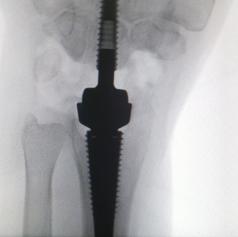

Pri posegu so uporabili večkomponentno protezo zapestja, ki je na trgu razmeroma nova, a se že izkazuje kot zelo učinkovita rešitev za bolnike z napredovalimi obrabnimi spremembami. Med operacijo kirurgi odstranijo poškodovane zapestne kosti, v dlančnici in koželjnici pripravijo natančno ležišče ter vanju vstavijo stabilno protezo. Ves kirurški poseg se sproti nadzoruje z rentgenskimi posnetki, kar zagotavlja visoko stopnjo natančnosti in varnosti. Operacija traja približno uro in pol, bolnik pa jo lahko opravi v regionalni ali splošni anesteziji.